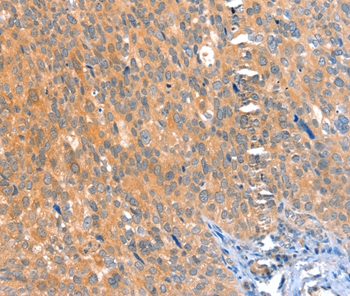

Immunohistochemical analysis of paraffin-embedded Human cervical cancer tissue using #36022 at dilution 1/25.